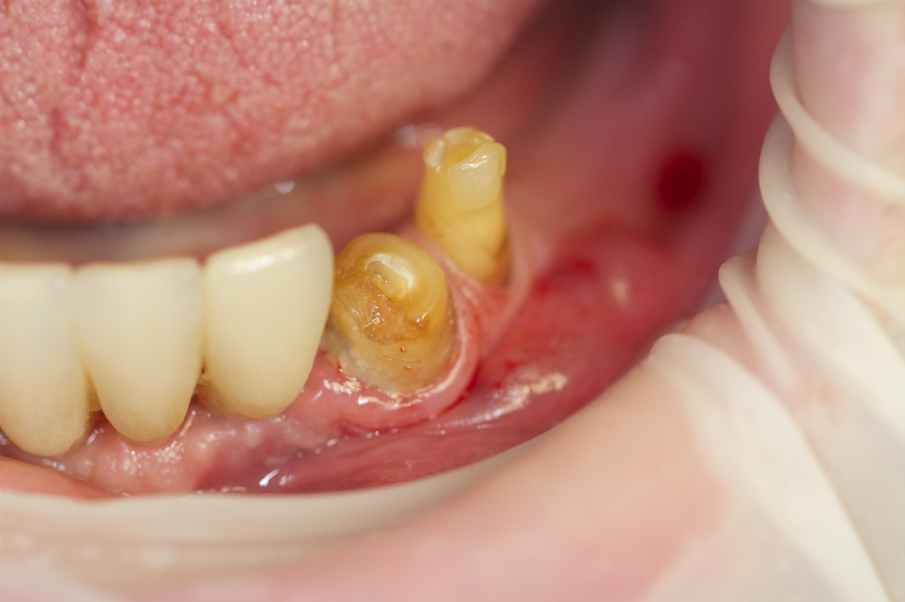

Fig. 3 - Dente fratturato 2.4.

Fig. 4 - Estrazione del dente 2.4.